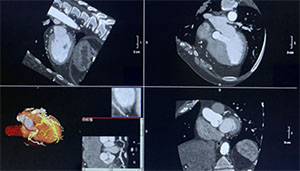

The Apex platform captures highly detailed images of the heart quickly, imaging the whole heart in a single cycle. With an ultra-wide detector and fast rotation speed, the scanner can acquire cardiac data in less than a second, reducing motion-related artifacts and improving diagnostic image quality.

“Coronary CT angiography gives us a detailed, noninvasive look at the coronary arteries in a matter of seconds,” said Dr. Matt Brady, Medical Director for imaging services at Roper St. Francis Healthcare. “Having this capability at Roper St. Francis Mount Pleasant Hospital helps us diagnose or rule out coronary disease sooner, which can speed treatment plans and reduce delays for patients who need answers.”